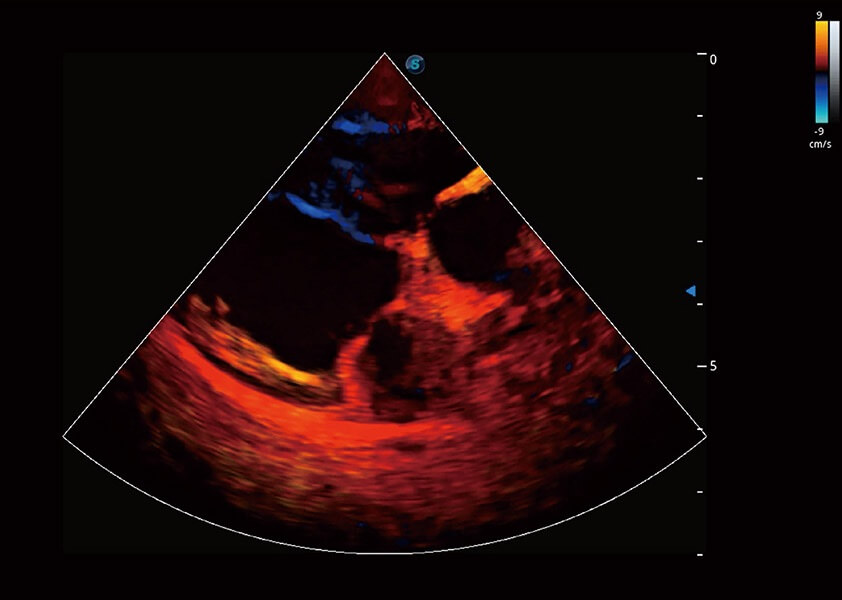

优异的基础图像

(犬)四腔心血流